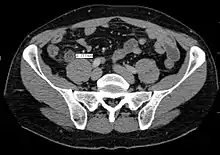

Computed tomography

Where it is readily available, computed tomography (CT) has become frequently used, especially in people whose diagnosis is not obvious on history and physical examination. Although some concerns about interpretation are identified, a 2019 Cochrane review found that sensitivity and specificity of CT for the diagnosis of acute appendicitis in adults was high.[49] Concerns about radiation tend to limit use of CT in pregnant women and children, especially with the increasingly widespread usage of MRI.[50][51]

The accurate diagnosis of appendicitis is multi-tiered, with the size of the appendix having the strongest positive predictive value, while indirect features can either increase or decrease sensitivity and specificity. A size of over 6 mm is both 95% sensitive and specific for appendicitis.[52]

However, because the appendix can be filled with fecal material, causing intraluminal distention, this criterion has shown limited utility in more recent meta-analyses.[53] This is as opposed to ultrasound, in which the wall of the appendix can be more easily distinguished from intraluminal feces. In such scenarios, ancillary features such as increased wall enhancement as compared to adjacent bowel and inflammation of the surrounding fat, or fat stranding, can be supportive of the diagnosis. However, their absence does not preclude it. In severe cases with perforation, an adjacent phlegmon or abscess can be seen. Dense fluid layering in the pelvis can also result, related to either pus or enteric spillage. When patients are thin or younger, the relative absence of fat can make the appendix and surrounding fat stranding difficult to see.[53]